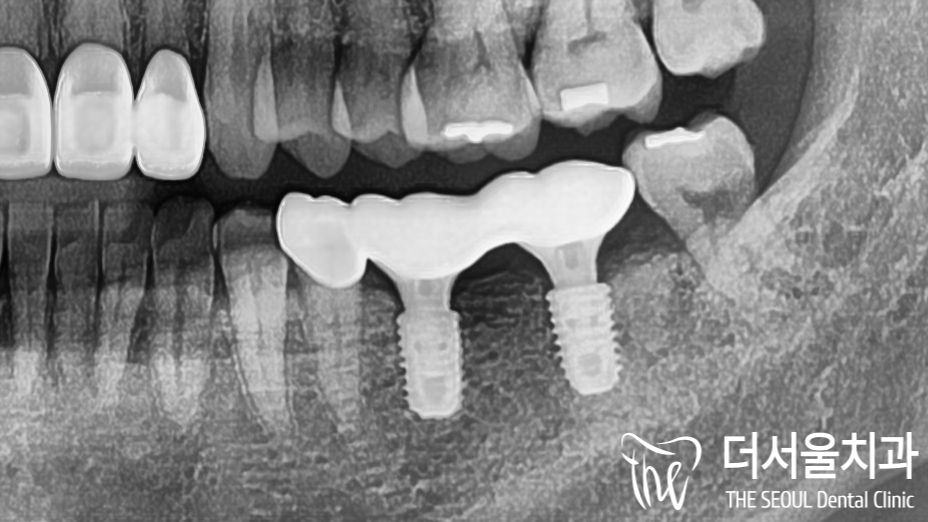

다행히 이전에 심어놨던 것은

안정적으로 심어져 있는 것을 볼 수 있는데요.

성남치과 에서는 빠져있는 임플란트 오른쪽 위,

10번대 식립을 도와드리기로 했습니다.

파노라마 사진을 보면

튼튼하게 심어져 있는 상악 어금니 픽스쳐의

모습을 확인할 수 있습니다^___^